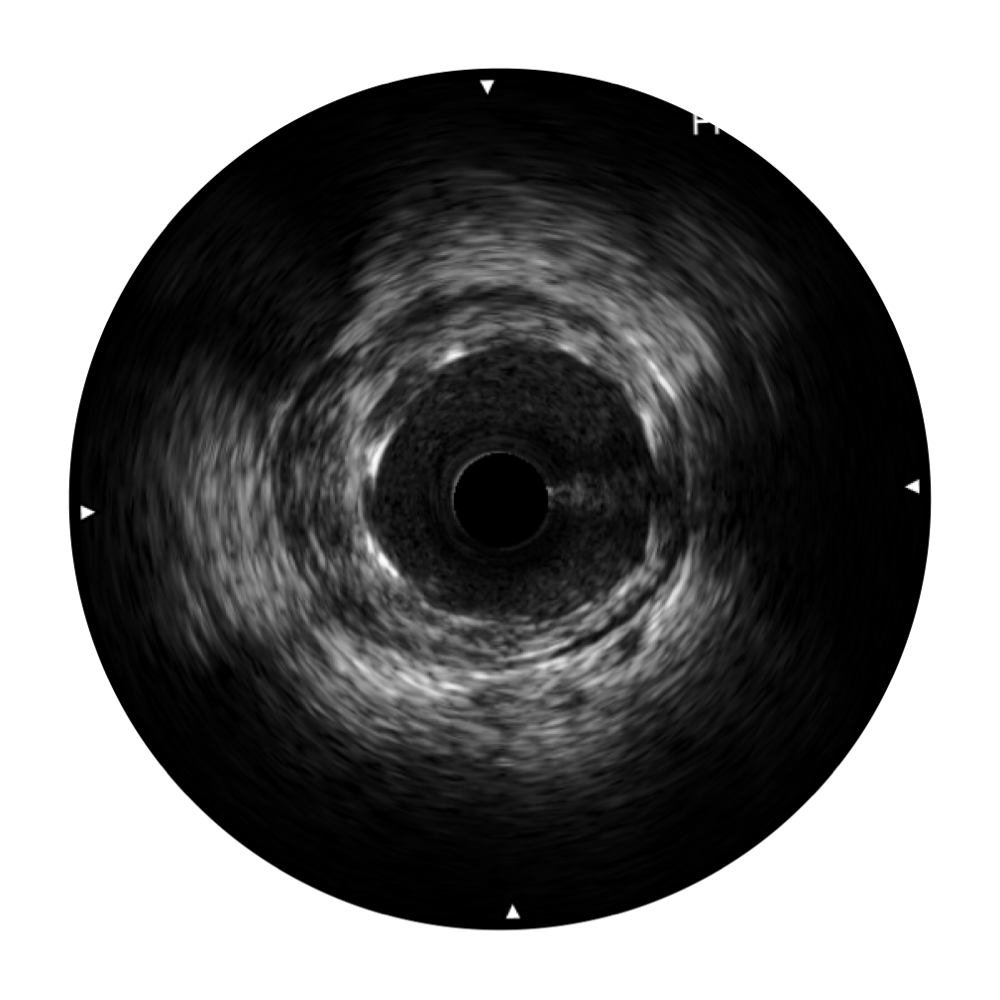

• 传统IVUS图像

对比传统IVUS导管成像,云顶集团官网宽频IVUS图像的近场支架梁显影更细腻,远场中膜外血管仍清晰可辨,兼顾远中近,兼顾分辨力与穿透深度